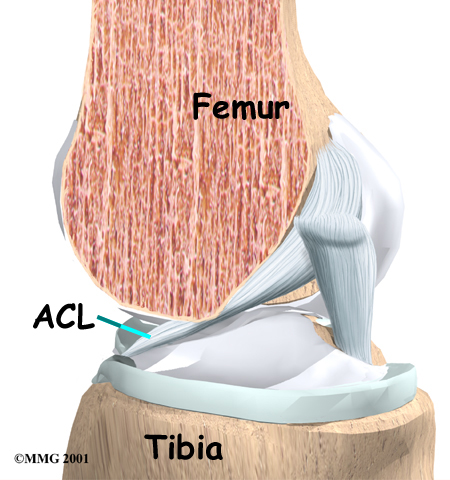

Ligaments are tough bands of tissue that connect the ends of bones together. The ACL is located in the center of the knee joint where it runs from the backside of the femur (thighbone) to connect to the front of the tibia (shinbone).

The ACL runs through a special notch in the femur called the intercondylar notch and attaches to a special area of the tibia called the tibial spine.